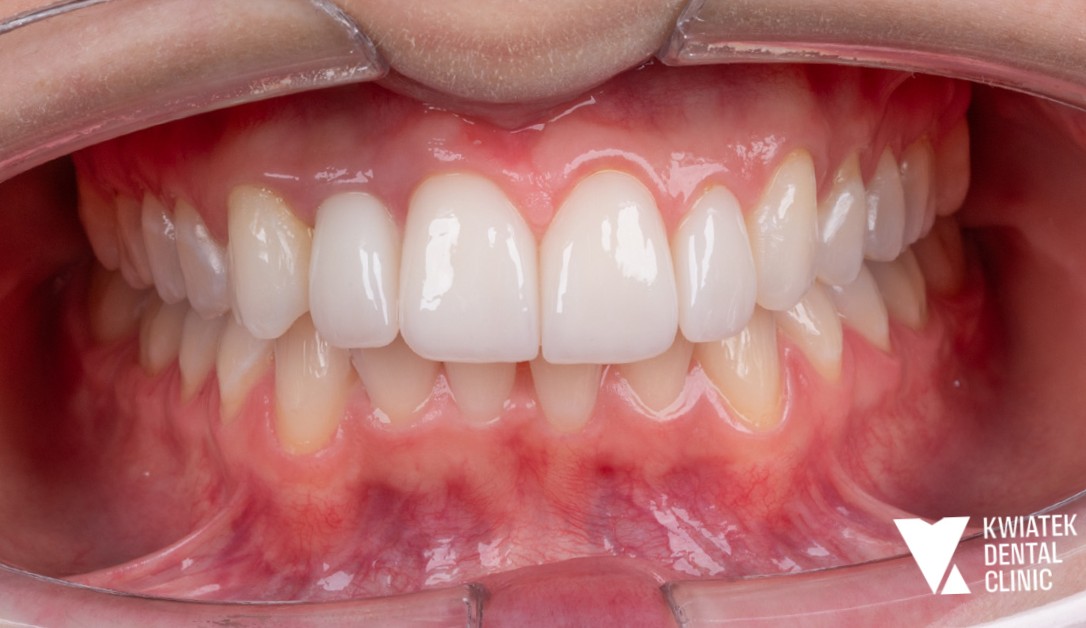

Pełna rekonstrukcja zwarcia i estetyki - historia wymagającej metamorfozy

Pacjent zgłosił się do kliniki z zaawansowanymi problemami stomatologicznymi: licznymi ubytkami próchnicowymi, brakami zębowymi, starciem zębów oraz zaburzeniami zwarcia. Leczenie obejmowało kompleksową diagnostykę, leczenie zachowawcze i endodontyczne, zabiegi chirurgiczne, implantację oraz wieloetapową odbudowę protetyczną. Efektem terapii jest perfekcyjnie zbalansowany zgryz, najwyższy komfort funkcjonowania oraz naturalnie piękny uśmiech, który podkreśla indywidualny charakter pacjenta i pozwala mu w pełni cieszyć się nim każdego dnia.